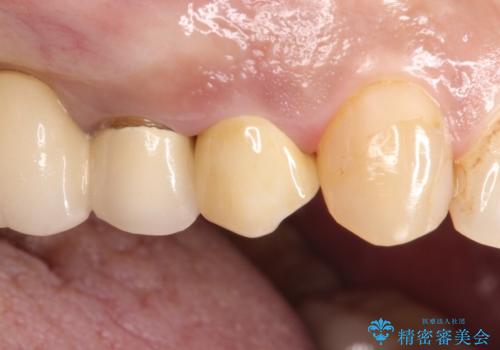

拡大鏡にて虫歯を除去。精度の高いセラミッククラウン

咬合力が強く、残存歯質が少ないためオールセラミッククラウンによる治療を行いました。

今回は白い材料での修復を希望されたため、欠けるリスクが高いセラミックインレーは避け、セラミッククラウンにて治療を行いました。